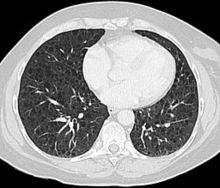

CT scan of the lungs in a patient with lymphangioleiomyomatosis showing numerous thin walled cysts within the lungs.

Computed tomography

The high-resolution computed tomography (HRCT) chest scan is better than the chest radiograph to detect cystic parenchymal disease and is almost always abnormal at the time of diagnosis, even when the chest radiograph and pulmonary function assessments are normal.[3][5][6][87] The typical CT shows diffuse round, bilateral, thin-walled cysts of varying sizes ranging from 1 to 45 mm in diameter.[5][6] The numbers of cysts varies in LAM from a few to almost complete replacement of normal lung tissue. The profusion of cysts tends to be milder in patients with TSC-LAM than S-LAM, perhaps explained in part because TSC-LAM patients typically receive earlier screening.[11] Pleural effusions are seen on CT in 12% of patients with S-LAM and 6% of patients with TSC-LAM. Other CT features include linear densities (29%), hilar or mediastinal lymphadenopathy (9%), pneumothorax, lymphangiomyoma, and thoracic duct dilation.[5][6] Ground-glass opacities (12%) suggest the presence of interstitial edema due to lymphatic congestion. In patients with TSC, nodular densities on HRCT may represent multifocal micronodular pneumocyte hyperplasia (MMPH) made up of clusters of hyperplastic type II pneumocytes.[79][88][89] MMPH may be present in males or females with TSC in the presence or absence of LAM, but not in patients with S-LAM.[90] MMPH is not typically associated with physiologic or prognostic consequences, but one case of respiratory failure due to MMPH has been reported.[91][92][93]